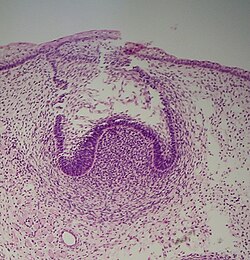

Rast i razvoj zuba prolazi kroz četiri stadij: stadij zametka, stadij kape, stadij zvona i stadij formiranja korijena.[1]

Stadij zametka počinje u šestom tjednu intrauterinog života ploda. Ektodermalni epitel zadebljava i formira epitelnu gredicu, koja se razvija i spušta u dubinu mezoderma. Ona se dijeli na vanjski i unutrašnji segment (primarna dentalna lamina) na kojem se u osmom tjednu počinju formirati zameci prvih mliječnih zuba (koji su ujedno i caklinski organ).

U stadiju kape započinje kalcifikacija caklinskog organa, proliferacija epitelnih stanica zametka u okolni mezoderm i invaginacija bazalnog dijela caklinskog organa.

U stadiju zvona se nastavlja proliferacija epitela i produbljivanje invaginacije u bazalnom području caklinskog organa. U udubljenje urasta mezoderm i formira dentalnu papilu, od koje će nastati zubna pulpa. Od mezenhimnih stanica razvija se folikularna vrećica, koja sa dentalnom papilom i caklinskim organom čini zubnu klicu.

Zubna pulpa sa periferno raspoređenim odontoblastima započinje stvaranje dentina (dentinogeneza), a caklinski organ pomoću ameloblasta stvaranje cakline (amelogeneza). Folikularna vrećica formira fibrovaskularnu kapsulu oko zuba u razvoju, koja je odgovorna za nutriciju, a ima i druge važne uloge. Na kraju stadija zvona počinje stvaranje kosti u mezodermu, folikul se transformira u periodontalno tkivo, a od caklinskog organa nastaje sekundarna dentalna lamina (za supstituentne zube). Također caklina i dentin formiraju zonu koja će postati caklinsko-dentinski spoj.

Stadij formiranja korijena se karakterizira stvaranjem strukture korjenova od Hertvigove epitelne ovojnice, koja nastaje u stadiju zvona od unutrašnjeg sloja caklinskog organa.